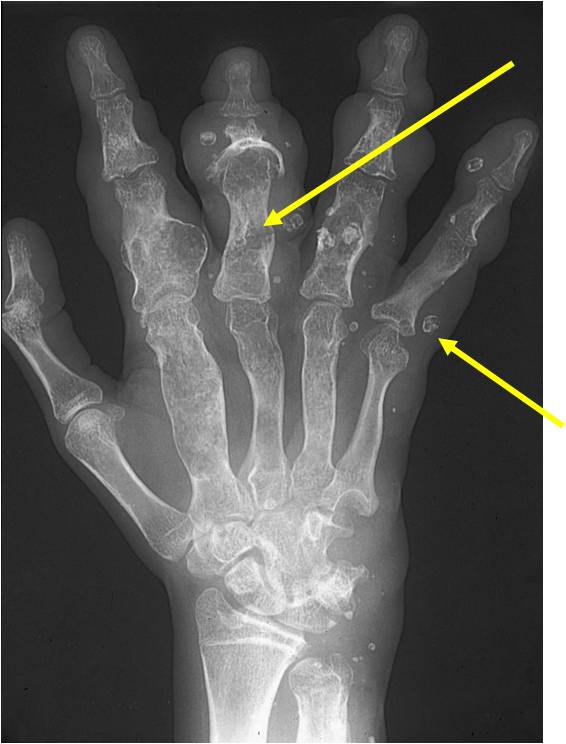

- 50% involve hands and feet (mostly phalanges)

- Localized, radiolucent defect usually with punctate calcifications

- Calcifications are typical but not always present

- Calcifications are stippled, punctate, popcorn like calcifications and “Ring and Arc” calcifications

- Cortex may be scalloped and thinned in the phalanges

- Geographic lytic lesion

- Expansile remodeling with thinned cortex

- Chondroid matrix with calcifications in majority of tumors

Enchondromatosis

- Enchondromatosis is a rare disorder that is not hereditary in which the patient is afflicted with multiple intraosseous cartilaginous tumors or enchondromas.

- May be predominantly unilateral or affect a single extremity/limb

- Affected limb is often shortened and deformed and angulated

Enchondromas in enchondromatosis may involve the metaphysis, diaphysis, epiphysis and articular cartilage